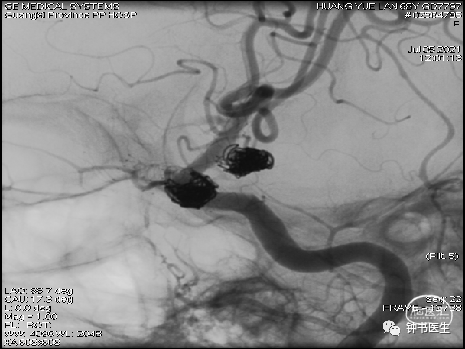

2021-06-22 DSA

R-ICA